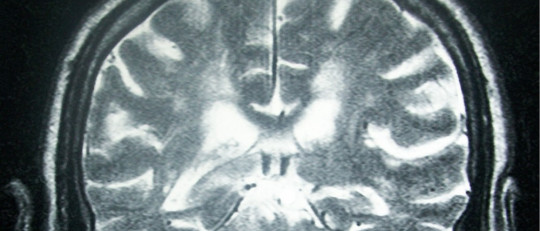

2. Microcefalia

Otro síntoma característico es la microcefalia, es decir, el hecho de que la capacidad del cráneo es significativamente menor de lo esperado para el rango de edad de la persona. Esto hace que el encéfalo no se desarrolle tal y como debería hacerlo.

Tanto a causa de las malformaciones del cráneo como por el desarrollo anormal del sistema nervioso, las personas con síndrome de Wolf-Hirschhorn suelen experimentar una clara discapacidad intelectual.

Las complicaciones en el funcionamiento del sistema nervioso hacen que las crisis convulsivas no sean raras. Estos episodios pueden llegar a ser muy peligrosos